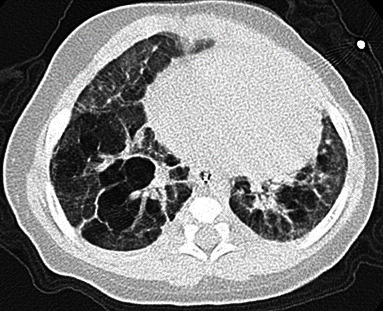

Home high-flow nasal cannula (HFNC) use in the neonatal field has become prevalent as a noninvasive respiratory support, but its application in home care remains rare. We report two cases in which a home HFNC was effective in managing extremely low-birth-weight infants with severe bronchopulmonary dysplasia (BPD). Case 1 was a male infant born at 22 weeks' gestation weighing 435 g. Case 2 was a female infant born at 23 weeks' gestation weighing 450 g. Both patients had mothers with chronic placental abruption or chorioamnionitis. They transitioned from invasive mechanical ventilation to nasal CPAP (nCPAP) at 45 days (case 1) and 50 days (case 2) old. Subsequently, at 324 days (case 1) and 90 days (case 2) old, they transitioned to a HFNC, demonstrating stable oxygenation and ventilation, but faced difficulty in removal. Considering the drawbacks of prolonged hospitalization, the patients were discharged using a home HFNC at 404 days (case 1) and 391 days (case 2) old. For case 1, the HFNC was set at 4 L/min of room air and 2 L/min of oxygen, whereas for case 2, it was set at 5 L/min of room air and 1 L/min of oxygen. These settings maintained an SpO2 above 90% and a pCO2 below 60 mmHg. An HFNC offers advantages over nCPAP owing to its lower invasiveness and reduced discomfort for long-term use. However, reports on the use of a home HFNC for BPD are scarce. In recent years, while premature infant mortality has decreased worldwide, the incidence of BPD has risen, necessitating preparedness for prolonged ventilation in preterm infants. Home ventilators represent a strategy to prevent extended hospitalization, and based on our cases, home HFNC for BPD appears safe and effective, making it potentially useful for managing preterm infants requiring prolonged respiratory support in the future.